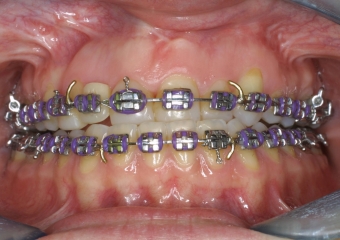

Imagem inicial - Clínica Cliniface

Imagem inicial

Imagem após cirurgia ortognática - Clínica Cliniface

Imagem após cirurgia ortognática